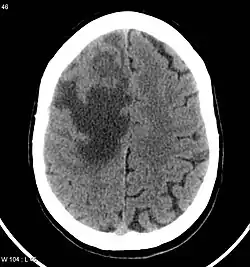

Brain CT scan showing CNS metastasis from the breast, the primary source.

Clinically, research evidence demonstrated that the primary tumours that have the greatest association with brain metastasis consist of lung, breast, melanoma, and colon cancers.[1][5] Despite the knowledge of sources, there is a lack of understanding regarding why these sources have increased predilection, nor an understanding of the mechanism difference behind each metastasis process.[1]

CNS metastases are diagnosed through imaging techniques that produce detailed images of the inside of the body, including parts such as the bones, organs, muscles, and nerves.[13] Magnetic resonance imaging (MRI) and computed tomography (CT) are two representative imaging procedures for this purpose.[12]

MRI scans use strong magnetic fields and radio waves to create an image, while CT scans use X-rays. MRI scans produce more detailed images of bodily structures, particularly soft tissues including the brain,[13] and are better at detecting CNS metastases than CT scans. However, CT scans are sometimes used for the initial imaging modality due to their lower cost and efficiency in screening for multiple conditions.[14]